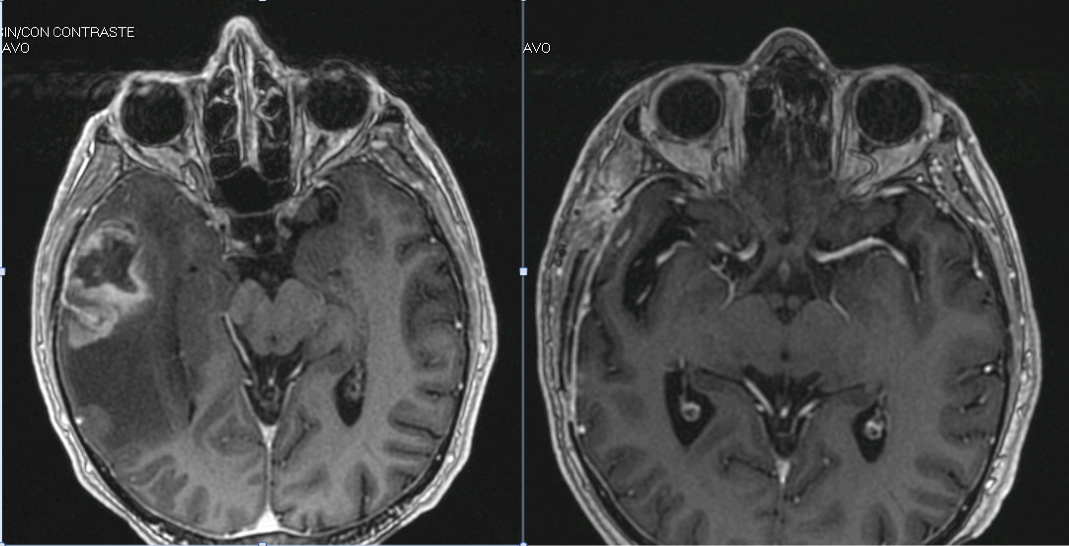

The problem is that tumor infiltration is often microscopic and not visible to the naked eye, so what appear to be complete resections in the surgeon's eyes are not in subsequent control MRI.